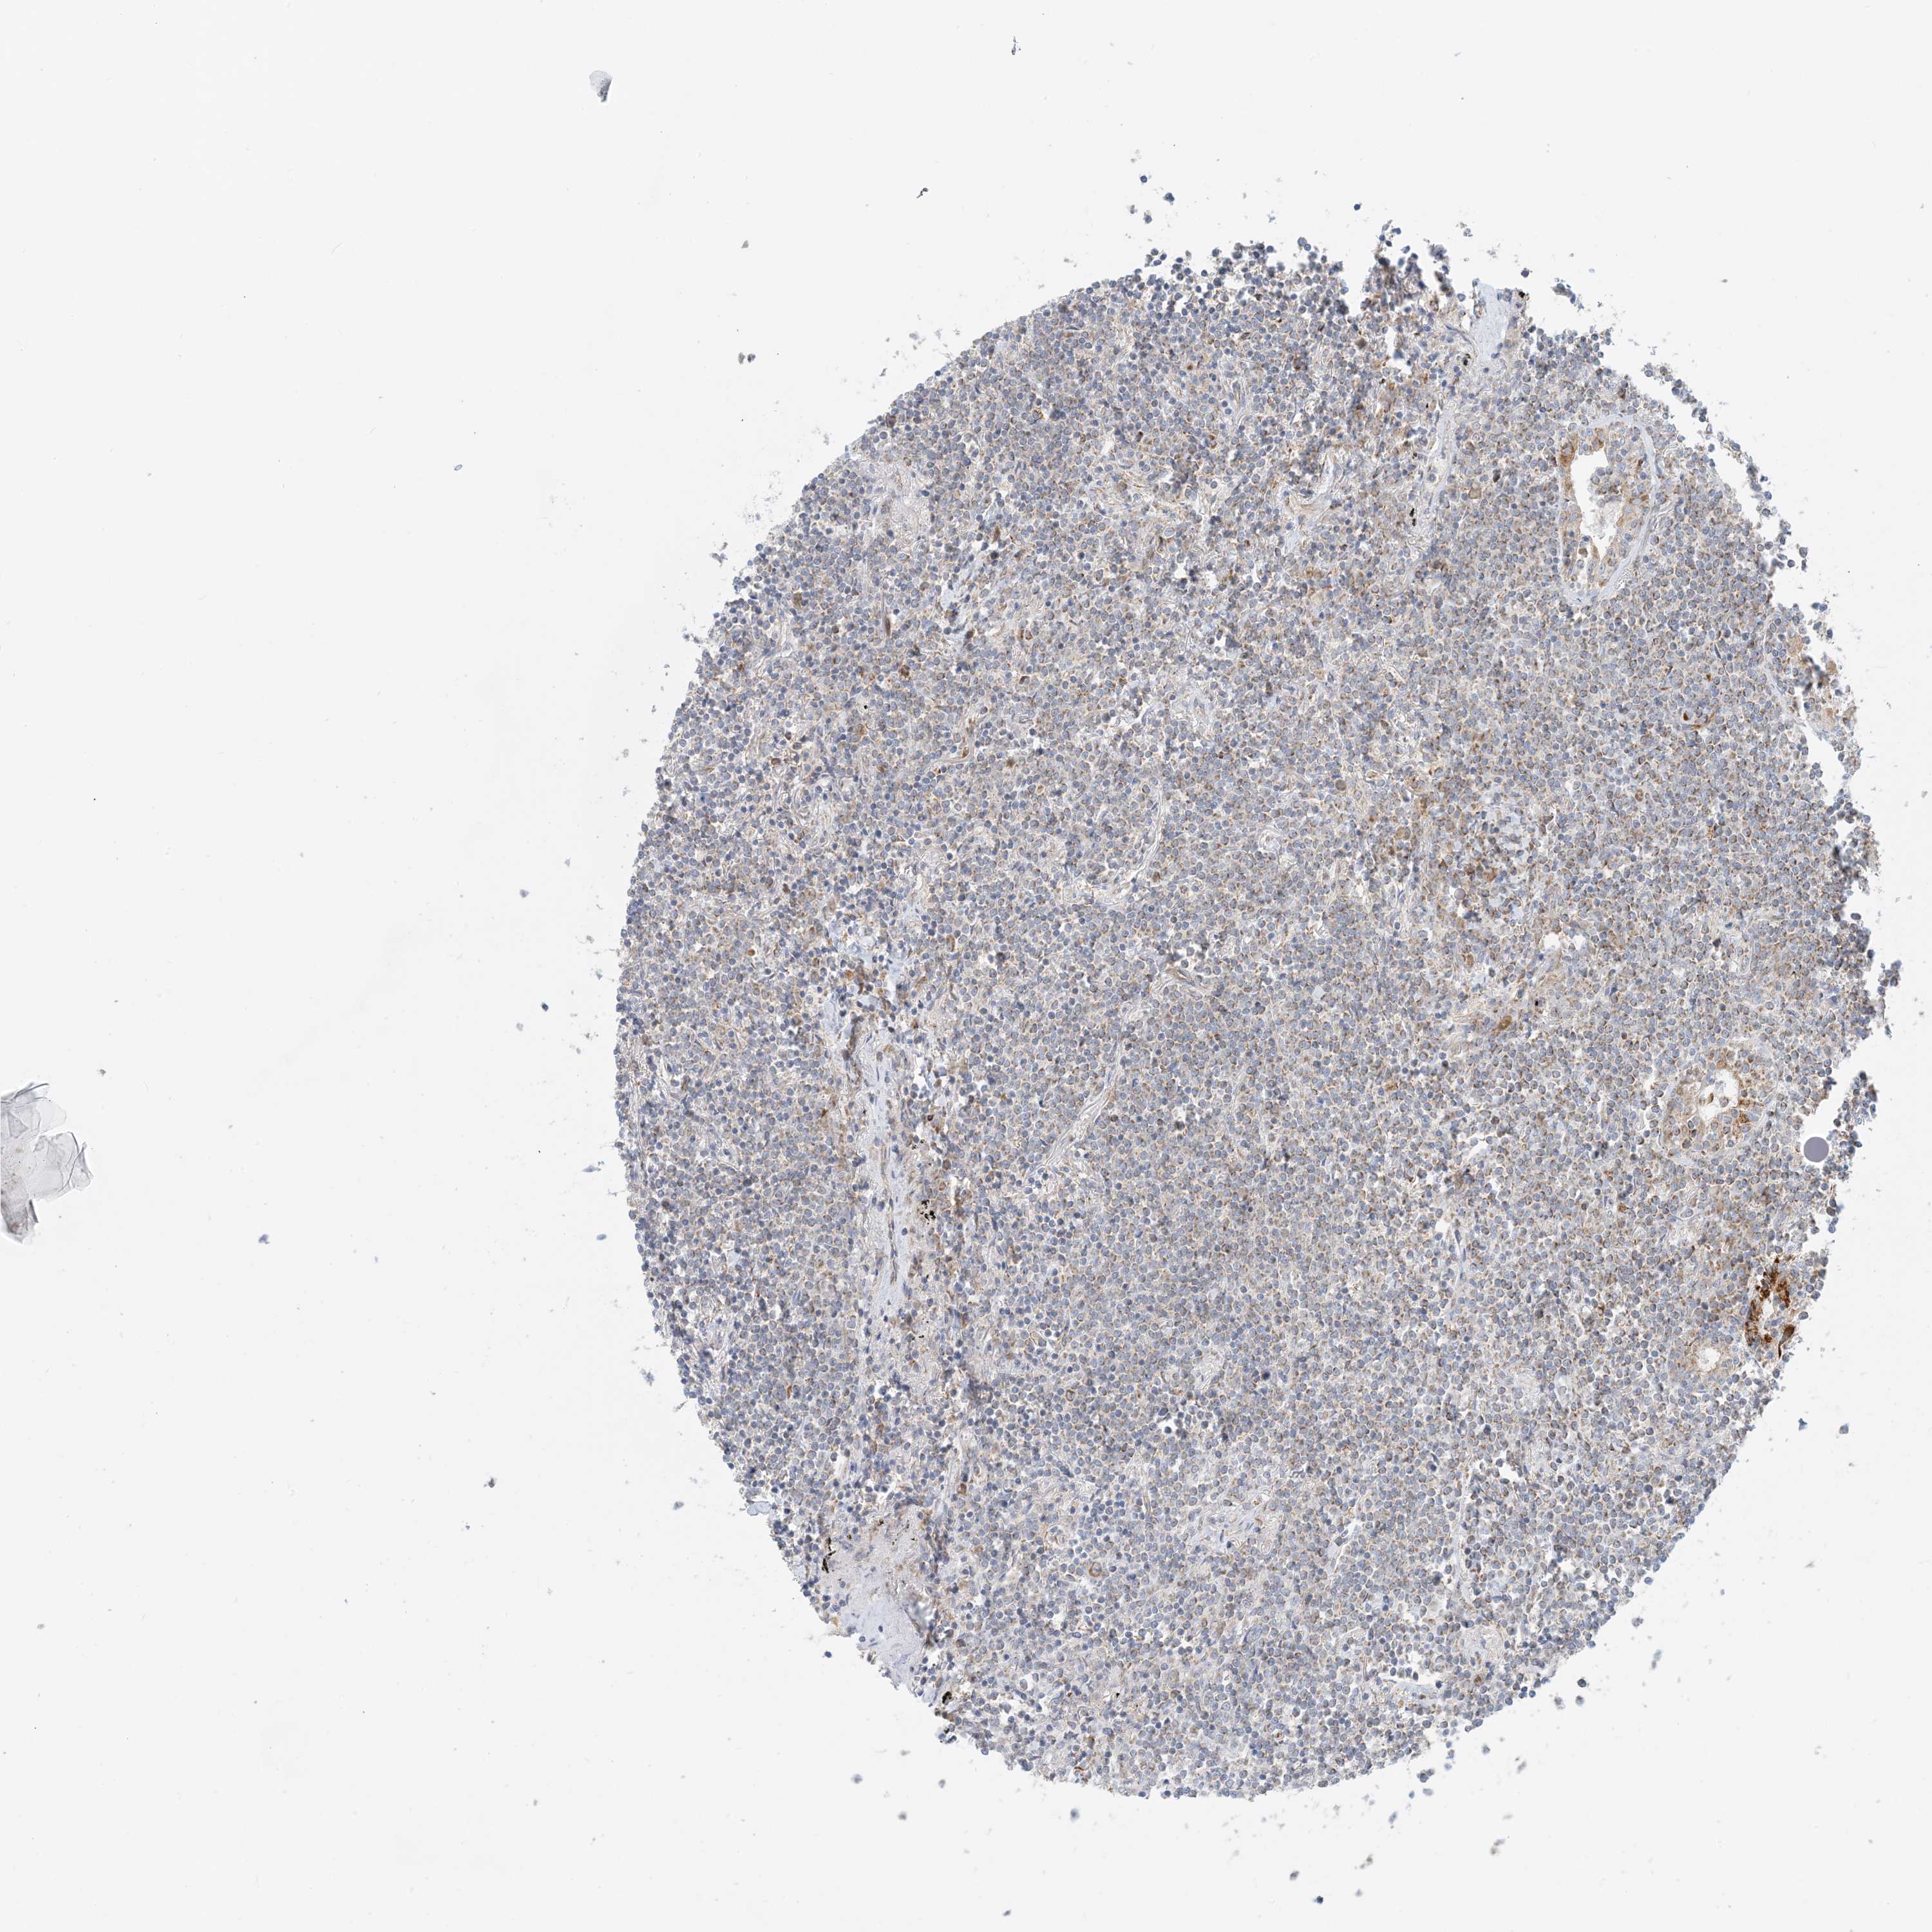

LYMPHOMA - Protein expressioni

A mouse-over function shows sample information and annotation data. Click on an image to view it in a full screen mode. Samples can be filtered based on level of antibody staining by selecting one or several of the following categories: high, medium, low and not detected. The assay and annotation is described here.

Antibody stainingi

Antibody staining in the annotated cell types in the current human tissue is reported as not detected, low, medium, or high, based on conventional immunohistochemistry profiling in selected tissues. This score is based on the combination of the staining intensity and fraction of stained cells.

Each image is clickable and will lead to virtual microscopy that enables deeper exploration of all samples and also displays staining intensity scores, fraction scores and subcellular localization as well as patient and tissue information for each sample.

Antibody HPA031966

Hodgkin's disease, NOS

Malignant lymphoma, non-Hodgkin's type, High grade

Malignant lymphoma, non-Hodgkin's type, Low grade